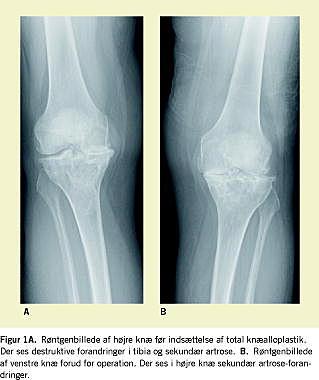

Ved den objektive undersøgelse fandtes i højre knæ en lille ekstensionsdefekt, fleksion til 120 grader og få graders valgusstilling. I venstre knæ fandtes normal ekstension og fleksion til 135 grader. Begge knæ var ligamentært stabile. Røntgenbillederne viste voldsomme destruktive forandringer ved tibia bilateralt samt sekundær artrose (Figur 1A og B ).

Hyppigst rammer steroidinduceret osteonekrose i knæet den vægtbærende del af femurkondylerne. I denne patients tilfælde var det kun den proksimale del af tibia, som var involveret som illustreret i Figur 1 A og B. Specielt hos yngre mennesker kan en tidlig erkendelse af osteonekrose i knæet og efterfølgende aflastning forhindre kollaps af den subkondrale knogle og dermed udskyde tidspunktet for en eventuel knæalloplastik.